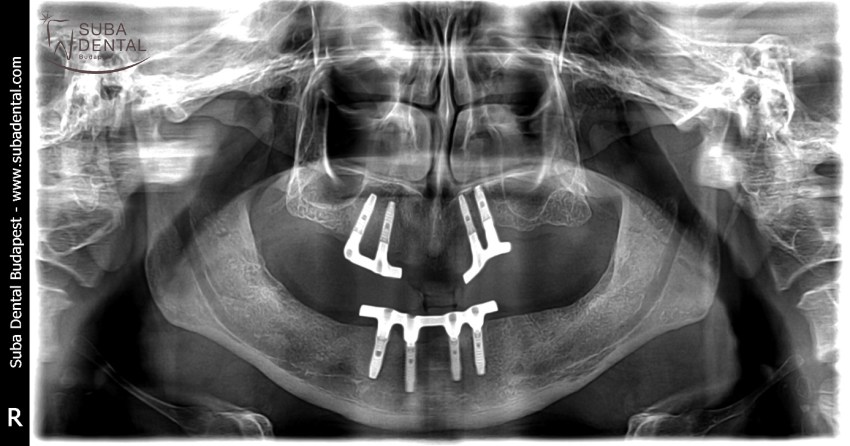

Panoramic radiograph of the lower and upper bar